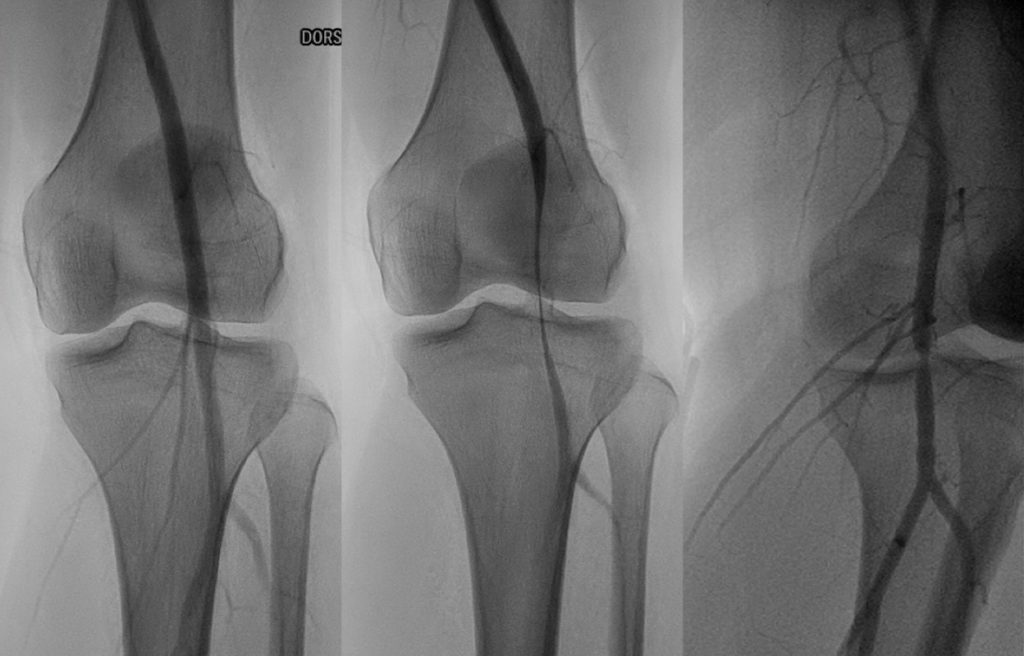

Popliteal entrapment syndrome is a rare condition in which the popliteal artery, which supplies blood to the lower leg and foot, is compressed or squeezed by nearby structures, such as the muscles and tendons at the back of the knee. This can cause reduced blood flow to the lower leg and foot, leading to pain, numbness, weakness, and other symptoms. It is most commonly seen in young athletes and can be treated with surgery or other interventions aimed at relieving the compression of the artery.